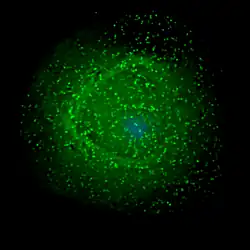

Zur Vermehrung benötigt das Virus Wirtszellen, die den CD4-Rezeptor auf der Oberfläche tragen.[79] Dies sind vor allem CD4-tragende T-Helferzellen (CD4+-Zellen). Als hauptsächliches Reservoir für die humanen Immundefizienz-Viren dienen die follikulären T-Helferzellen in den Lymphfollikeln des Körpers, die rund zwei Prozent der CD4+-Zellen ausmachen.[80][81] T-Helferzellen unterstützen andere Weiße Blutzellen bei immunbiologischen Prozessen, wie der Reifung der B-Lymphozyten zu Plasma- und Gedächtniszellen oder der Aktivierung zytotoxischer T-Lymphozyten und Makrophagen. Neben T-Lymphozyten besitzen auch Monozyten, Makrophagen und dendritische Zellen CD4-Rezeptoren. Latent infizierte ruhende CD4+-T-Zellen (T-Gedächtniszellen) stellen langlebige Reservoire für HIV dar und sind der Grund, dass HIV trotz wirksamer antiretroviraler Medikamente bisher nicht eradiziert werden kann und es nach Absetzen der Therapie immer wieder zu Rezidiven kommt.[82][83][84]